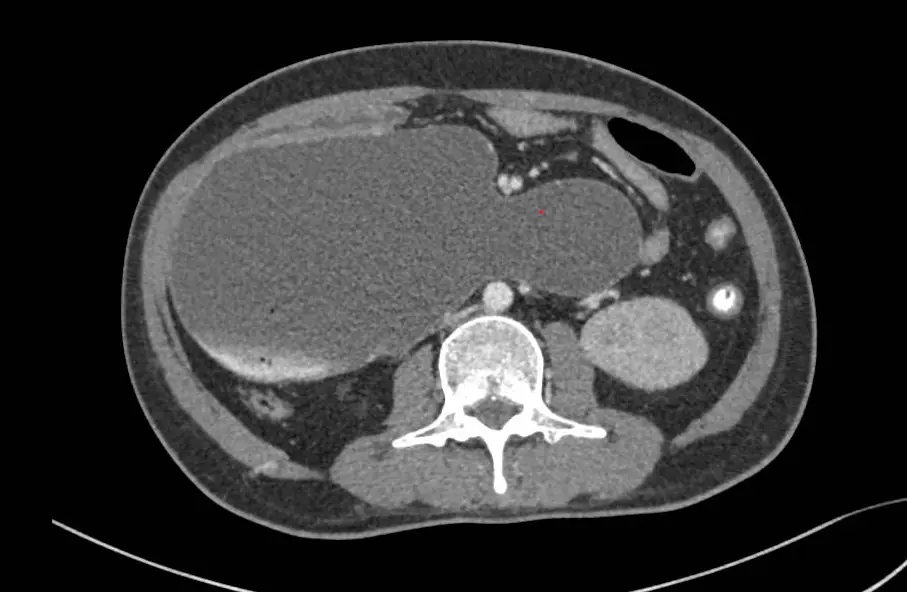

Anh Y.C.S. (42 tuổi, Campuchia) nhập viện FV trong tình trạng nguy kịch: nôn ra máu, sốc do thiếu máu và thiếu dịch, cơ thể suy kiệt, bụng chướng to bất thường. Kết quả CT scan khiến các bác sĩ kinh ngạc: dạ dày, tá tràng đã giãn cực đại, chiếm gần toàn bộ khoang bụng.

“Tá tràng là đoạn đầu tiên của ruột non, nối với dạ dày, dài khoảng 25cm. Ở người bình thường, tá tràng trong trạng thái xẹp, kích thước to chừng ngón tay, khi thức ăn đi vào thì giãn ra bằng đầu ngón chân cái. Riêng bệnh nhân này, khẩu kính tá tràng đo được có đường kính 12cm, chu vi 38cm, to bằng ống tay áo”, bác sĩ Thái cho hay.

Một dấu hiệu khá lạ và có ý nghĩa ghi nhận trong quá trình theo dõi ở ca bệnh này, đó là dạ dày đã xẹp và co lại rõ rệt sau khi đặt ống thông mũi – dạ dày – tá tràng 3 ngày, nhưng tá tràng thì không. Tá tràng vẫn giãn cực đại, dính vào các cơ quan xung quanh, gần như chiếm trọn không gian nội tạng phần bụng chậu và mất hoàn toàn chức năng co bóp.

Hình ảnh chụp cắt lớp vi tính: tá tràng giãn khổng lồ chiếm gần hết khoang bụng

Hình ảnh chụp cắt lớp vi tính: tá tràng giãn khổng lồ